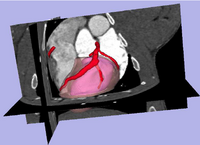

Risk Mass Estimation for Heart Risk EvaluationPrognosis and treatment of cardiovascular diseases frequently require the determination of the myocardial mass at risk caused by coronary stenoses. However, few work has been done for estimating the myocardial mass at risk directly from the heart surface segmented from CAT imagery, rather than using a simplified heart model such as ellipsoid. More... New: L. Zhu, Y. Gao, A. Yezzi, C. Arepalli , A. Stillman, and A. Tannenbaum. A Computational Framework for Estimating the Mass at Risk Caused by Stenoses using CT Angiography, Internatial Journal of Cardiac Imaging(IJCI), In preparation. New: L. Zhu, Y. Gao, V. Mohan, A. Stillman, T. Faber, A. Tannenbaum. Estimation of myocardial volume at risk from CT angiography, Proceedings of SPIE , pp.79632-38A, 2011. | |